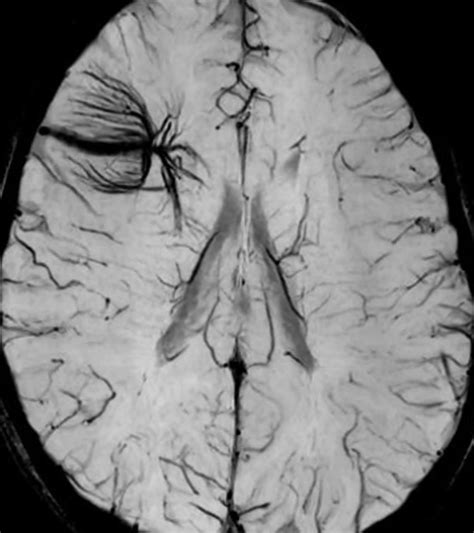

Diagnosing a DVA typically involves imaging studies, such as magnetic resonance imaging (MRI) or computed tomography (CT) scans. These imaging techniques can reveal the characteristic appearance of DVAs, which include:

• Abnormal venous channels

• Dilated venous structures

• Caput medusae appearance, where the venous channels radiate outward like the head of Medusa

In some cases, additional imaging studies, such as angiography, may be performed to better visualize the venous drainage patterns and rule out other vascular malformations.